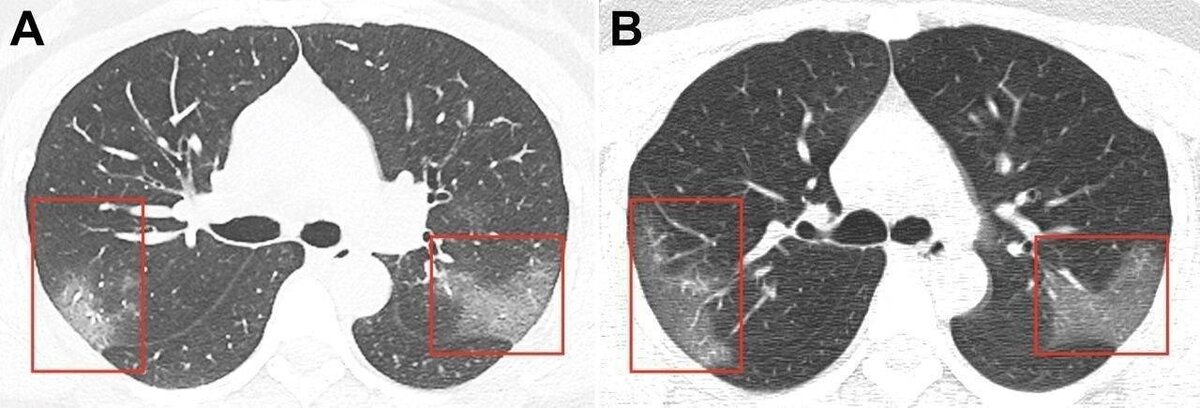

Пациентка – 33-летняя женщина из Китая. На одном снимке видны помутнения на легких. На другом, сделанном три дня спустя, видно, что пораженная область расширяется.